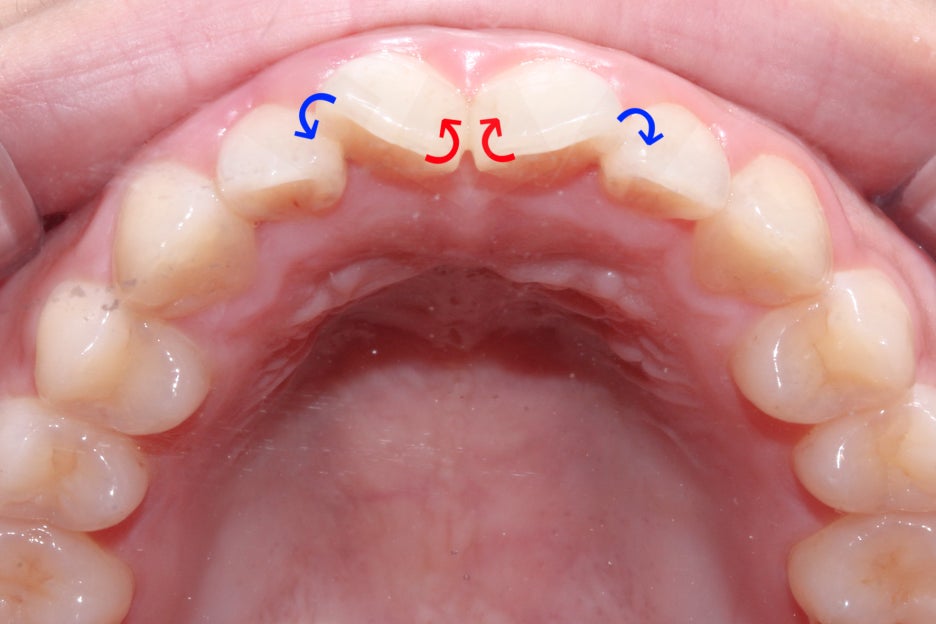

옥니교정을 하기 위해서는 위처럼 회전된 중절치를

바른 각도로 바꾸는 것이 중요한데요,

중절치가 마주보고 있는 면을 순측으로 빼내고

뻐드러진 바깥 부분을 설측으로 당겨

치아의 각도를 조정하기로 하였습니다.

옥니교정을 위해서 지난 5개월 간 위와 같은

장치를 사용하여 중절치의 치축을 돌리는 과정을 진행하였는데요,

뻐드러진 중절치의 바깥면을 설측으로 당겨오기 위해

파워체인을 걸어 당기는 힘을 지속적으로 가하였습니다.

또한 중절치가 마주보고 있는 부분은 오픈코일스프링을 사용하여

공간을 넓혀주어 치열이 자연스러운 U자 모양을 형성할 수 있도록 하였는데요,